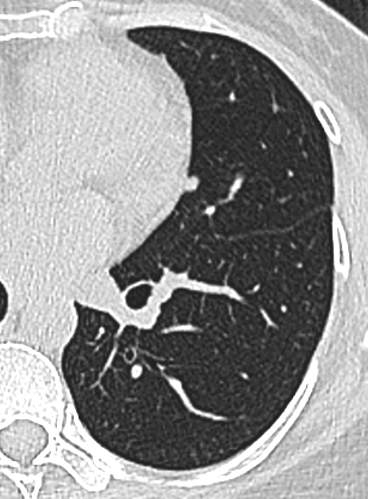

23年初复查CT左下肺GGO有所增大,直径:6.9mm

问题来了,一年多后复查GGO有增大,考虑恶性吗,需要手术吗,病理考虑什么?